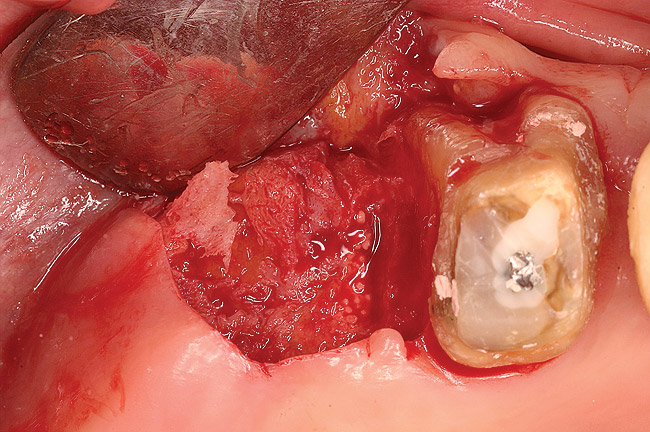

Thirty patients were selected on the basis of need for dental extractions with bone preservation and/or augmentation in the socket before the placement of a dental implant. These patients were cleared medically for oral surgical procedures. Preoperative clinical photographs and periapical radiographs were taken. After administration of local anesthesia, full-thickness labial and lingual/palatal flaps were elevated. Minimal soft-tissue manipulation was performed to allow visualization of the entire alveolar crests and debridement of fenestrations and/or dehiscence defects, if present. Elevation of each tooth or retained roots was performed, using periotomes, luxatomes, proximators, root forceps, and any other instruments and procedures as required to extract the tooth with minimal trauma (Figure 1). After extraction and thorough debridement of the socket by mechanical means, clinical photographs were taken. The sites then were grafted with a resorbable β-TCP of small particle size, 150 µm to 500 µm (Cerasorb) (Figure 2). This material has been used and reported in the literature for almost 30 years as a viable bone graft in orthopedic and other surgical specialties. In this study, the granules of β-TCP were mixed thoroughly with blood from the surgical sites and the sockets filled to ideal contours faciolingually and apicocoronally. The grafts and adjacent 3 mm of alveolar bone then were covered with resorbable collagen barriers (BioMend®, www.zimmerdental.com) (Figure 3). The flaps were repositioned and the areas closed with an appropriate number and type of sutures. No attempts were made to obtain primary closure over the exposed barriers. Postoperative radiographs and clinical photographs were taken. Subsequently, sutures were removed at 1 to 2 weeks.

Figure 1  Occlusal view after extraction of tooth No. 27 using Piezosurgery<sup>®</sup> (Piezosurgery Inc, www.piezosurgery.com) and thin-bladed elevators.

Figure 1